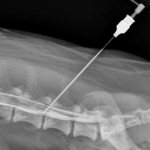

- Визуализирующие методы

. При первичном обследовании пациентов с жалобами на холодный пот информативно УЗИ органов брюшной полости и малого таза. При наличии сопутствующей симптоматики показано рентгенологическое исследование грудной клетки и живота. Иногда назначают компьютерную томографию или МРТ.